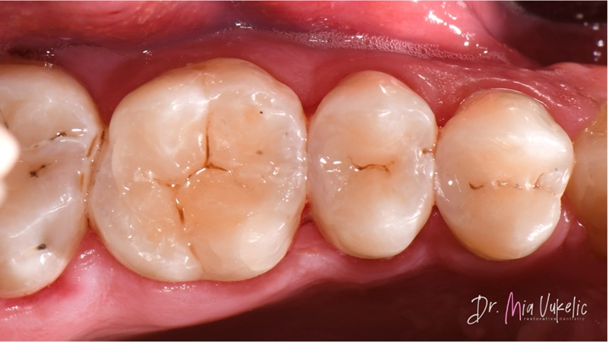

Nach dem Polieren wurde die Füllung mit einem Oberflächenversiegler (PermaSeal™ Kompositsversiegler, Ultradent Products) beschichtet. Danach erfolgte die abschließende Kontrolle mittels Okklusalprüfung und Röntgenaufnahme.

Auf den finalen Fotos wird deutlich, dass Transcend Universalkomposit der Restauration ein außergewöhnlich ästhetisches Erscheinungsbild verleiht. Das Halo Teilmatrizensystem ermöglichte zudem die Herstellung einer hervorragenden approximalen Anatomie, wie die Röntgenaufnahme belegt.